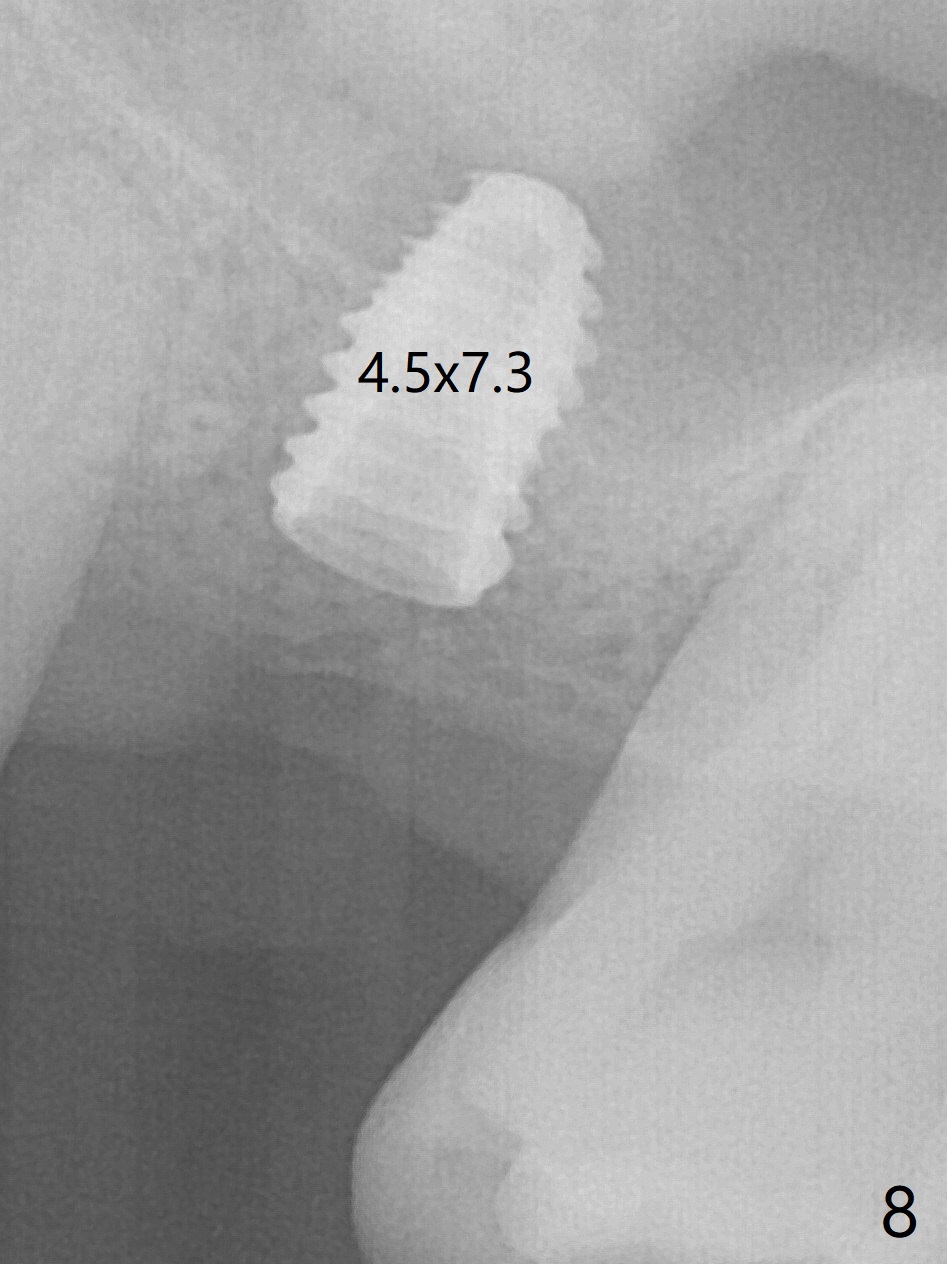

Trajectory of sinus lift without guide at #14 is off (Fig.1 (Magic Sinus Lifter (L) for 9 mm (gingival level)) and needs to be corrected (Fig.2 long line) by re-using 4.8 mm Magic Drill. Following placement of PRF membrane and Demineralized Cortical Allograft (.125-.850 mm) for sinus lift (Fig.3 black dashed line), a 4x10 mm dummy implant is placed with off trajectory. The latter will be fixed by using Lindmann bur to remove the bone distal (Fig.4). The result is less satisfactory with placement of 4.5x10 mm dummy implant (Fig.5). It appears necessary to initiate a new osteotomy (Fig.6 long black line). In fact the result is appealing (Fig.7). The final implant (5x7.3 mm) seems to be placed ideally shown by PA (Fig.8) and BW (Fig.9). Immediately postop CT demonstrates distal defect (Fig.10 *;3-D) and supracrestal placement palatal (Fig.11 P; coronal section). More allograft is then placed in these 2 areas. In all, it is difficult to establish a correct osteotomy without guide. The patient return for uncover 3.5 months postop, although there is a small hole in the middle of the incision (Fig.12). The crown/abutment becomes loose less than 1 month post cementation when the patient chews something tough. It is more related to the unfavorable implant/crown ratio. It is loose again 2 months later. Screw driver is buried inside the abutment with plumber tape. When it is loose for the 3rd time 13 months post cementation, the existing screw driver with a created slot (for retention) is buried without plumber tape after retorque at 35 Ncm (Fig.13). A tissue-level implant should have been used.